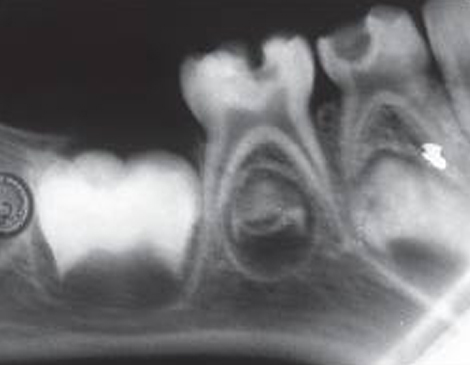

root canal endodontic treatment root canal endodontic treatment root canal endodontic treatment